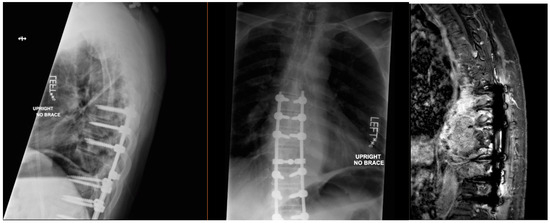

Pathology described an atypical eosinophilic osteoid-secreting lesion containing abundant osteoblasts with vascular structures, consistent with an osteoblastoma. There was no malignant mitotic activity identified. However, it was not possible to rule out osteosarcoma, making the differential diagnosis at that time osteoblastic osteosarcoma vs. aggressive osteosarcoma (Figure 2).

Figure 2. Pathology demonstrates an atypical eosinophilic osteoid-producing lesion (H and E, 400×).

The extensive spread throughout the spine and considerable central canal stenosis warranted aggressive surgery. The patient underwent a T7–L1 posterior spinal arthrodesis with allograft bone and instrumentation, accompanied by thoracic laminectomies at T9, T10, and T11, as well as a left-sided T10 costotransversectomy to decompress neural structures and stabilize the spine. However, not all of the tumor could be resected due to unfavorable surgical risk. Follow-up imaging over the subsequent 3 years demonstrated recurrence and progression, with the patient developing weakness in his legs, prompting emergency T10 corpectomy, laminectomy of T9–T11, T7–L1 post spinal arthrodesis with allograft bone, bilateral T10 neurotomy, and right-sided transpedicular decompression for circumferential decompression of the spinal cord. Further serial imaging again indicated serial tumor progression, and it was concluded that his spine showed stability but he was no longer a candidate for further surgery (Figure 3).

Figure 3. The first two images were taken in March 2019, with the right image taken in July 2023. Other MRIs were taken, which demonstrated serial occurrence.